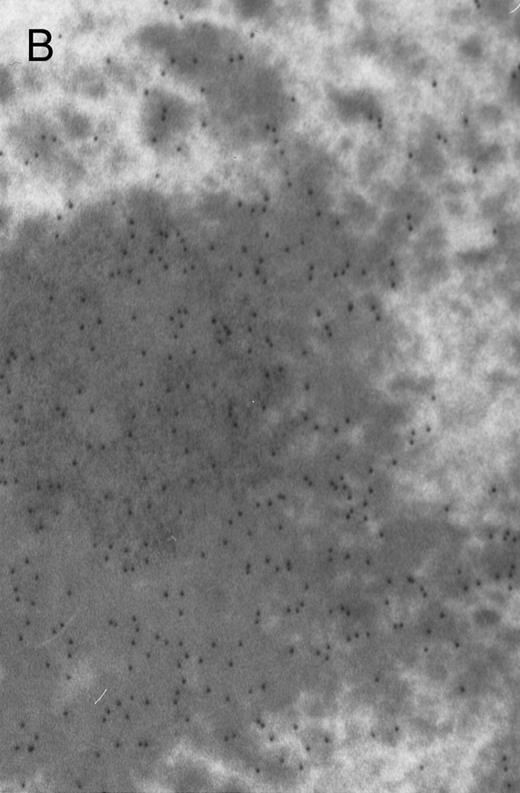

In both cases no. 1 and no. 2, electron microscope studies demonstrated electron-dense inclusions in 30% of early and late polychromatic erythroblast sections and many marrow reticulocytes. In ultrathin sections that reacted with monoclonal antibodies to either α- or β-globin chains followed by gold-labeled anti-mouse IgG, the density of gold particles over the majority of the inclusions was clearly greater than that over surrounding inclusion-free cytoplasm (Fig 3). By contrast, in sections from the two patients with β-thalassemia major, gold particles were concentrated over the inclusions following incubation with the antibody to α-globin chains, but not to β-globin chains (Fig 4A-C). The density of gold particles over inclusions in all control preparations was not greater than that over surrounding cytoplasm (Fig 4D).

Electron micrographs of erythroblastic inclusions from sections of marrow immunogold-labeled with mouse monoclonal antibody. Inclusions from case no. 1 show positive reactions with antibody against α-globin chains (A) and β-globin chains (B). Inclusions from case no. 2 show positive reactions with antibody against α-globin chains (C) and β-globin chains (D). Magnifications: A, × 32,000; B, × 38,000; C, × 32,000; D, × 37,000.

Prominent intra-erythroblastic inclusions were also present in both of these individuals (patients no. 1 and 2) with dominantly inherited β thalassemia. The percentage of polychromatic erythroblast sections containing inclusions in the two cases was 30%, which is considerably above the range (0.2% to 2.8%) previously reported in β-thalassemia trait.13 We have investigated the composition of the inclusions in cases no. 1 and 2 by immunoelectron microscopy using mouse monoclonal antibodies against human α- and β-globin chains and the immunogold technique. The intra-erythroblastic inclusions in the two cases reacted with both monoclonal antibodies to α- and β-globin chains, clearly indicating that these inclusions contained both types of chains. In contrast, the intra-erythroblastic inclusions found in homozygous β thalassemia reacted with the monoclonal antibody against α globin but not β-globin chains, confirming that they consisted only of precipitated α-globin chains. These data support the hypothesis that the cellular pathology underlying the dominantly inherited β thalassemias is related to the synthesis of highly unstable β-globin chains, which are not able to form functional tetramers. These abnormal β-chain variants precipitate intracellularly together with the concomitant excess α-globin chains to form large inclusions, which leads to more severe ineffective erythropoiesis than in heterozygous β thalassemia, in which much smaller amounts of precipitated globin chains are found.17